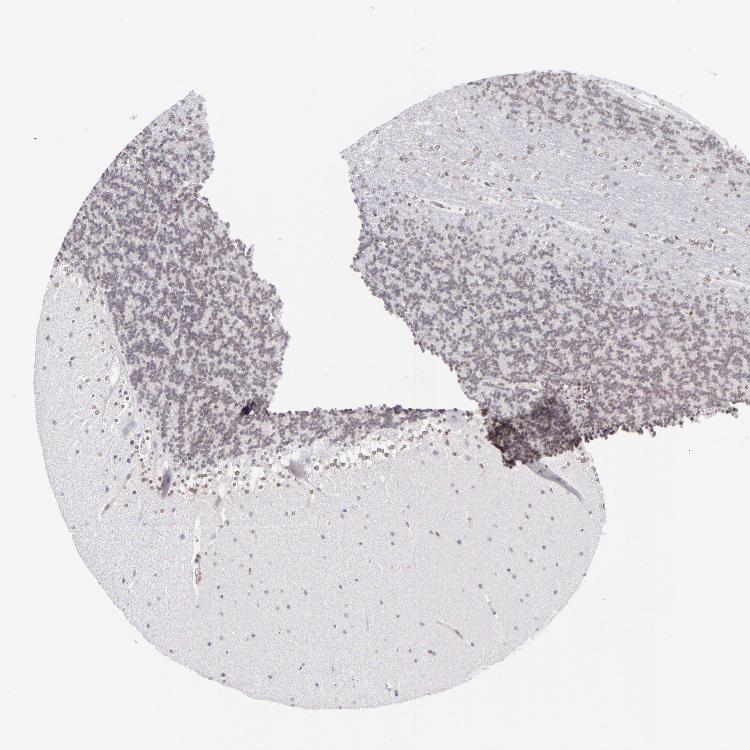

CEREBELLUM - Antibody stainingi

Antibody staining in the annotated cell types in the current human tissue is reported as not detected, low, medium, or high, based on conventional immunohistochemistry profiling in selected tissues. This score is based on the combination of the staining intensity and fraction of stained cells.

Each image is clickable and will lead to virtual microscopy that enables deeper exploration of all samples and also displays staining intensity scores, fraction scores and subcellular localization as well as patient and tissue information for each sample.

Antibody HPA000609Antibody CAB001545Antibody CAB002029Antibody CAB062552

Purkinje cells Not detectedNot detectedNot detectedNot detected

Cells in granular layer Not detectedNot detectedNot detectedNot detected

Cells in molecular layer Not detectedNot detectedLowNot detected